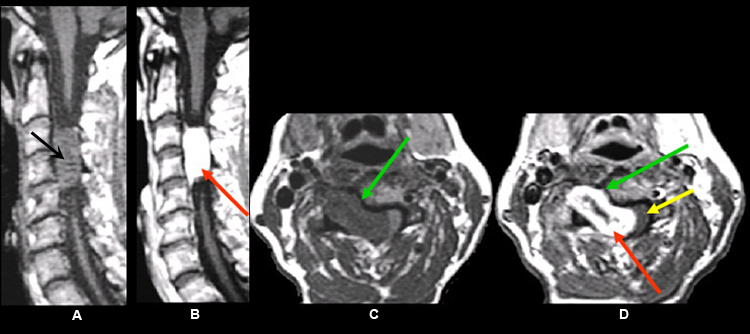

Imaging findings: Figure 4

- Pre-contrast sagittal T1wtd. MRI of cervical spine

- hypointense intradural mass (black arrow)

- Post-contrast (C+) sagittal T1wtd. MRI

- an enhancing intradural nerve sheath tumor (red arrow)

- Pre-contrast axial T1wtd. MRI

- hypointense dumbbell shape intradural mass (green arrow)

- Post-contrast axial T1wtd. MRI (C+)

- red arrow points to an enhancing intradural nerve sheath tumor

- yellow arrow points to cord compression

- green arrow points to the dumbbell shape of tumor with intraspinal component producing cord compression and paraspinal tumor extension through an enlarged neural foramen

Final impression:

- Dumbbell shape of tumor with intraspinal component producing cord compression and paraspinal tumor extension through an enlarged neural foramen following the exiting nerve root. This is characteristic of nerve sheath tumor.

- An enhancing intradural extramedullary nerve sheath tumor.

Imaging findings are consistent with schwannoma. |